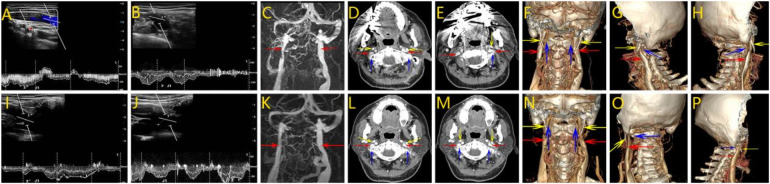

Methods: Three patients with imaging-confirmed compressive IJVS underwent Doppler ultrasound, 3D computed tomography venography, and magnetic resonance imaging. All patients receivedtargeted surgical decompression via resection of the compressive bony structures, with one patient receiving adjunctive venous stenting due to persistent flow limitation.

Results: All patients achieved significant postoperative improvement, including resolution of head noise and amelioration of associated symptoms. Imaging confirmed improved venous caliber and outflow. Notably, one patient with previous stenting failure benefited from staged decompression and re-intervention, highlighting the value of individualized management.